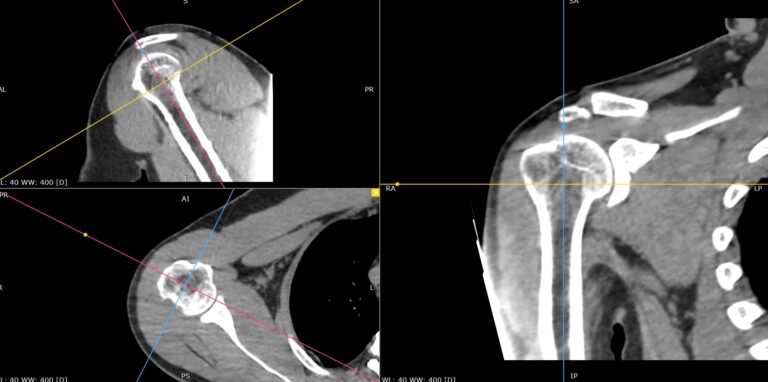

Мультиспиральная компьютерная томография является современным лучевым методом исследования, который позволяет с помощью рентгеновского излучения получить посрезовые снимки и после цифровой обработки создать объемные модели исследуемой области в мельчайших подробностях. Рентгеновские лучи в большей степени поглощаются плотными тканями организма, поэтому на снимках хорошо визуализируются кости скелета. Для более детальной оценки состояния мягкотканных структур зачастую проводится контрастное усиление.

В наших медицинских центрах КТ мягких тканей конечностей выполняется на современных мультиспиральных компьютерных томографах экспертного уровня TOSHIBA AQUILION. Аппараты послойно сканируют область исследования, одномоментно выполняя множество тончайших срезов. В результате получаются снимки высокого качества и трехмерные модели с изображением костного скелета и мягких тканей конечностей. При этом методика скоростного мультисрезового сканирования обеспечивает минимальную дозу рентгеновского облучения для пациента.